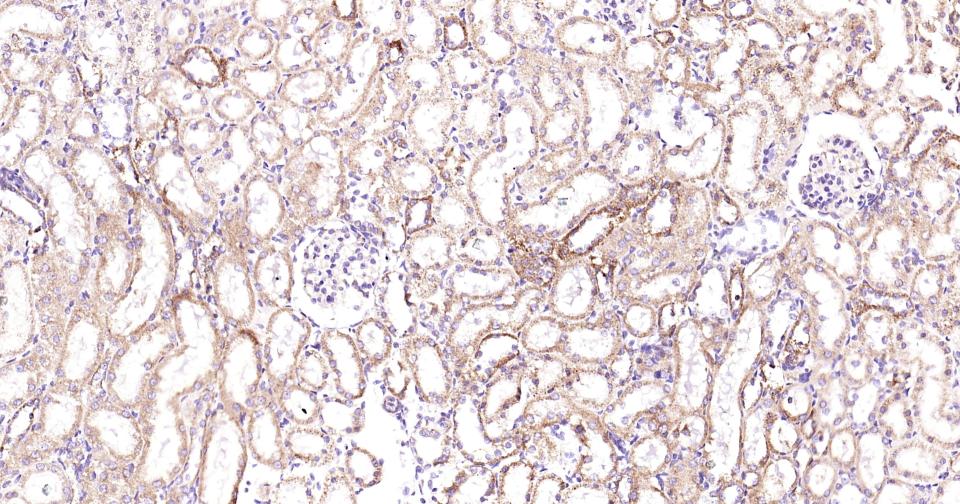

Paraformaldehyde-fixed, paraffin embedded Rat Kidney; Antigen retrieval by boiling in sodium citrate buffer (pH6.0) for 15 min; Antibody incubation with PIK3C3 Monoclonal Antibody, Unconjugated(bsm-61161R) at 1:200 overnight at 4°C, followed by conjugation to the SP Kit (Rabbit, SP-0023) and DAB (C-0010) staining.